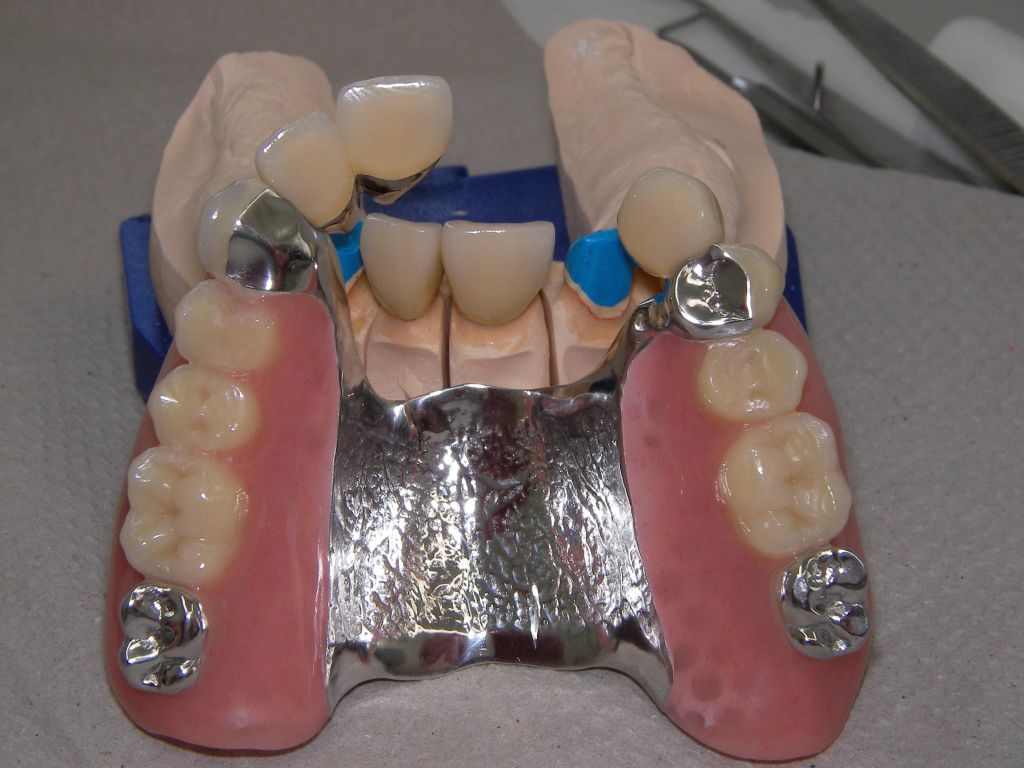

Besonderen Spaß macht mir großer, kombiniert festsitzend-herausnehmbarer Zahnersatz (sogenannter Kombi-Ersatz), auch mit Implantaten, weil er interessante Herausforderungen an den Behandler stellt. Diese Behandlungen sind oft langwierig, weil ein Behandlungsschritt auf dem anderen aufbaut: Häufig Parodontaltherapie, Wurzelkanalbehandlungen, Füllungstherapie, Implantate, erst am Ende Zahnersatz. Ob der Fall zur Zufriedenheit des Patienten gelöst werden konnte, stellt sich dann oft erst nach Monaten heraus. Hier ein einfacher Fall, bei dem keine besondere Vorbehandlung notwendig war. Der Patient, 58jährig, suchte die Praxis erstmals im September 2005 auf. Es erfolgten mehrere prothetische Planungen, der Gutachter des "Medizinischen Dienstes der Krankenkassen" (MDK) wurde noch von der Krankenkasse in Anspruch genommen, was heute bei größeren Planungen der Regelfall geworden ist. Umgesetzt wurde dann eine für einen solch großen Fall preisgünstige Lösung von 6434 Euro Gesamtkosten (4264 € Laborkosten, 2170 € Honorar). Die Krankenkasse übernahm als Festzuschuß 3843 €, für den Patienten verblieben 2591€. Im Januar 2006 ging es dann endlich los - zunächst allerdings beim Kieferchirurgen, weil wegen einer erhöhten, medikamentös bedingten Blutungsneigung es sicherer erschien, einige Zahnentfernungen von diesem durchführen zu lassen. Ausgangsbilder:

Das Hauptproblem dieses Falles lag im Oberkiefer - die über die Jahrzehnte abgeknirschten, kurzen Zähne erschweren Kronen, die durch eine Prothese belastet werden können. Die gewählte Lösung besteht darin, die Zähne nur rundherum zu beschleifen, aber nicht mehr zu kürzen und die Prothese mit einem Druckknopfsystem an die Zähne anzukoppeln, das ein "Spiel" aufweist, so daß die Prothese nicht als Hebelarm auf die schwachen Restzähne wirken kann. Rechts die beschliffenen Zähne kurz vorm Zementieren der Kronen.

Links das Bild zeigt das Metallgerüst, das später mit Keramik verblendet wurde. Um eine einfache Mundhygiene ebenso wie eine hohe zahntechnische Präzsion zu erreichen, wurden risikobehaftete Verblockungen minimiert. Rechts die Ästhetikeinprobe bei entspannter Oberlippe.

Links Bilder des Oberkiefers, rechts des Unterkiefers. Die Arbeit wurde von dem Dentallabor "Heitmeyer Zahntechnik", Osnabrück, gefertigt. Dem Labor ist hier für die hervorragende Arbeit zu danken, dem Patienten für die Freigabe der Bilder!

Die Zähne auf der Prothese sind aus verarbeitungstechnischen Gründen auch heute meist noch aus Kunststoff, auch wenn teurere Keramikzähne möglich wären. Kunststoff verschleißt über die Jahre, der Biß verändert sich. Um letzteres zu verhindern, sind hier zusätzlich Metallkauflächen eingearbeitet, die sich nicht verändern werden.

Auch Verbindungselemente verschleißen. Um den Verschleiß reparieren zu können, sollte der Verschleiß aus dem Mund in die Prothese gelenkt werden. Im Mund deshalb hier 4 harte Titankugeln, die passenden Druckknöpfe in der Prothese aus Kunststoff, wo sie leicht ausgewechselt werden können.